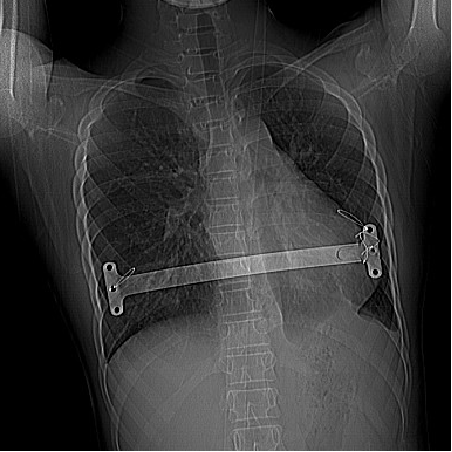

一步一步看懂漏斗胸nuss手术

新作为 新篇章】墨玉县人民医院成功实施首例重度漏斗胸微创矫形手术

14岁男孩漏斗胸微创手术治疗

漏斗胸微创手术(nuss手术

漏斗胸手术图片

漏斗胸微创手术